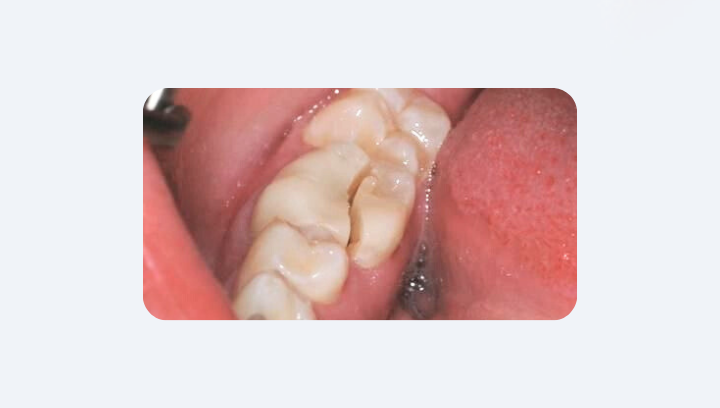

Почему старые пломбы нужно менять

Пломба — это не раз и навсегда. Даже лучший материал имеет свой срок службы. Металлические амальгамы, которые ставили 20–30 лет назад, и композиты старого поколения постепенно теряют плотность прилегания. По краям образуются микротрещины, которые становятся входом для бактерий. Кариес под пломбой развивается скрытно, и человек может не подозревать о нём годами. Именно поэтому у пациентов «со стажем» — тех, кому пломбы установили десятилетия назад — мы чаще всего видим скрытые поражения.

Пищевые привычки. Не стоит забывать и о механических факторах. Если у пациента есть привычка грызть семечки, лёд или орехи, старая пломба часто становится «слабым звеном» и ломается первой. Поэтому изменение пищевых привычек продлевает жизнь не только пломбам, но и самим зубам.

Современные решения. Замена старой пломбы — это не только «залатать дырку». Современные материалы, например керамические накладки (онлеи), позволяют не просто восстановить зуб, но и правильно распределить жевательную нагрузку. Такая реставрация может продлить срок службы зуба на 15–20 лет, сохраняя и функцию, и эстетику.